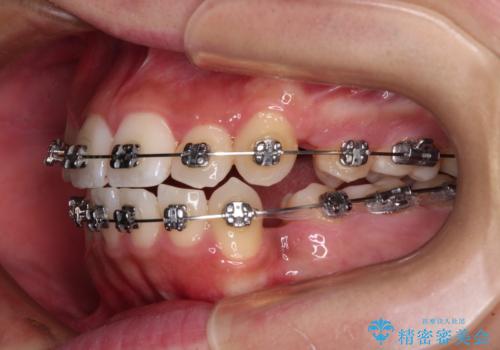

- メタルブラケット

- 2年4ヶ月

- 10-30回

上下ともに八重歯が顕著であり、前歯のクロスバイトがあったため、上下左右の第一小臼歯4本を抜歯し、ワイヤー装置での抜歯矯正を行うこととしました。